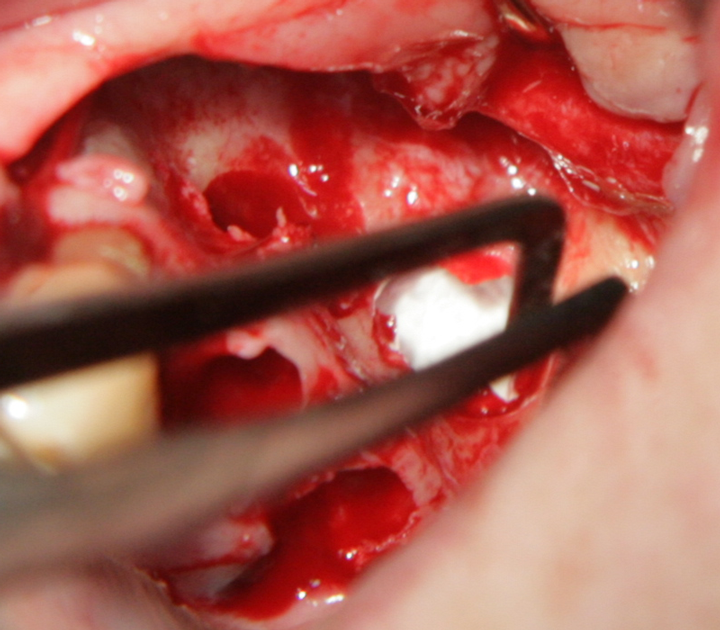

Отворен максиларен синус в началото на интервенцията. Случаят е интересен със следното - твърде атипична форма на трепанационния отвор. На какво се дължи на това - на лошо планиране на оперативния достъп или на нещо друго? Дължи се на факта, че отначало въпросната намеса беше планирана като балонен синуслифт; за съжаление обаче мембраната на синуса се разкъса и надуването на балона стана невъзможно.